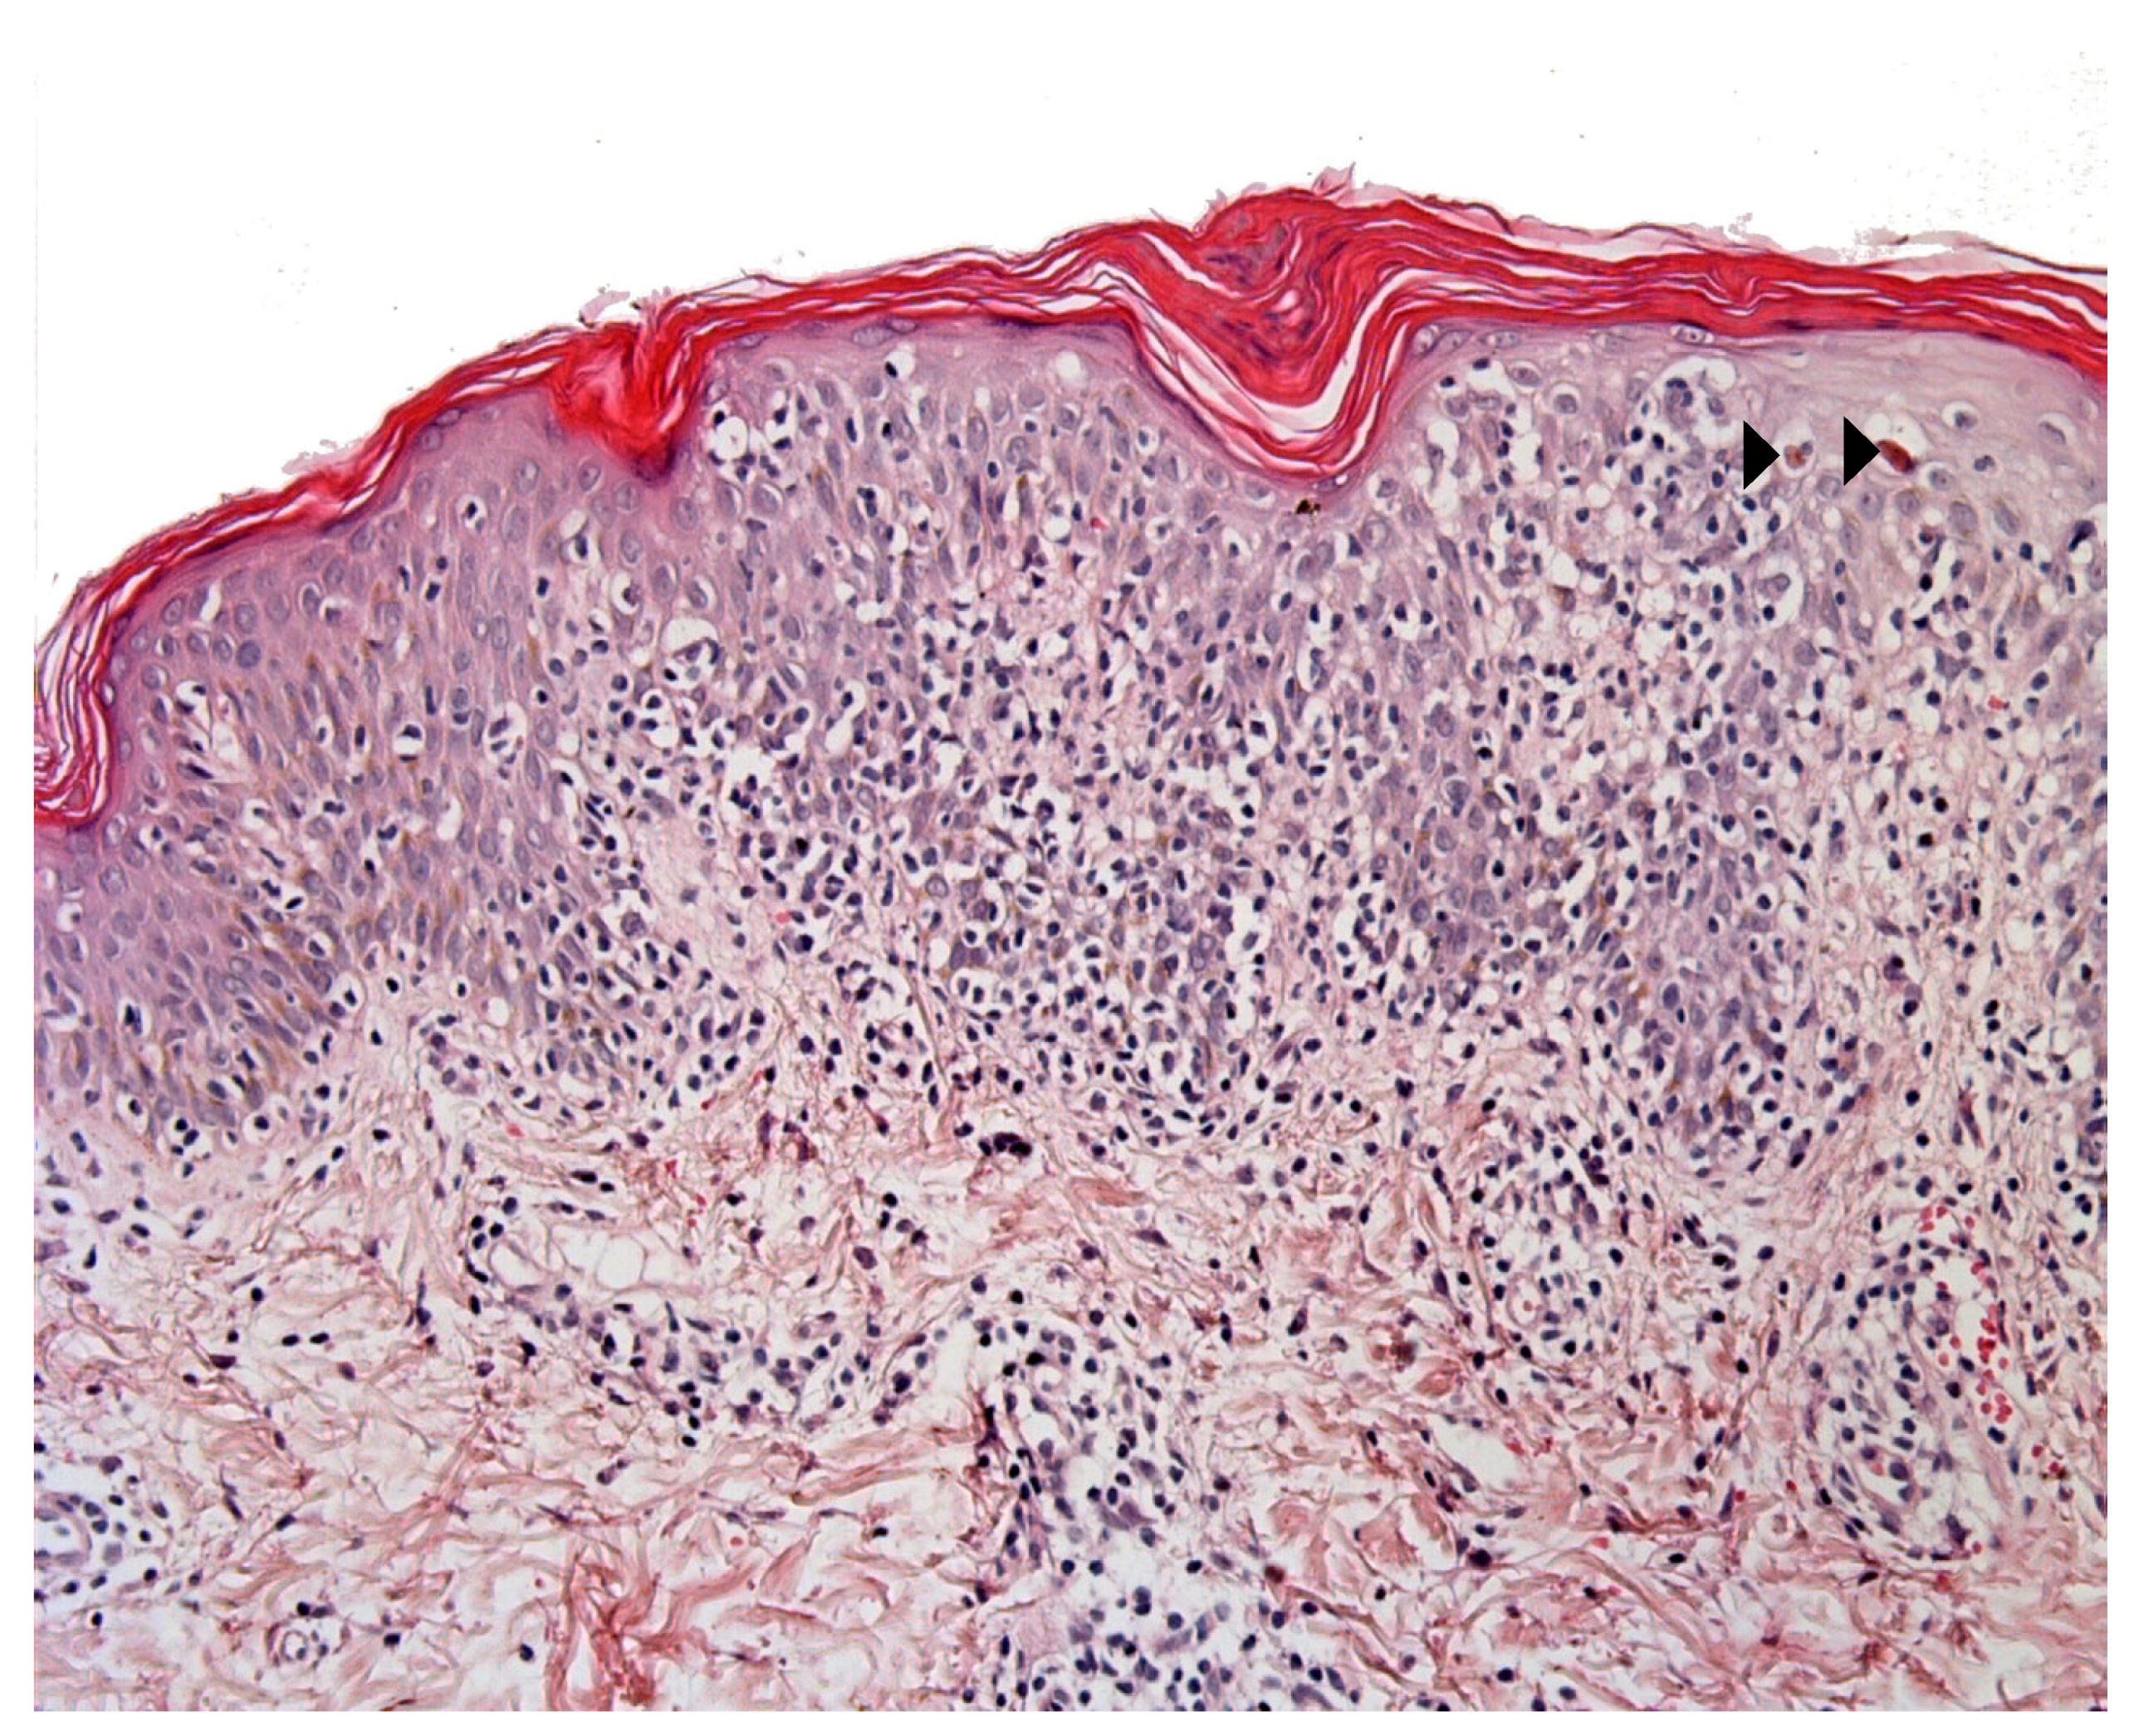

2.2. Immunodeficiencies Rashes